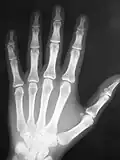

A typical image is shown in Figure 3.10. It can be seen that bone has a brighter shade of grey than that of the enveloping tissue and is brighter still than the surrounding air. This is the conventional method of displaying a radiograph such that higher photon attenuation is encoded as a brighter shade of grey.

From our earlier discussion, we can expect bone to absorb X-rays preferentially relative to the surrounding tissue and that the energy of these X-rays should have a strong influence on this absorption difference. It is this difference which generates contrast in radiographic images, and we can therefore expect contrast to reduce with increasing X-ray energy. We can also expect that the influence of scatter should be apparent at all X-rays energies.